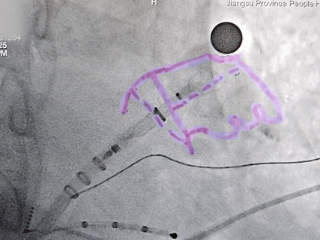

MemoLefort封堵器展开后DSA下造影评估

输送鞘轴向不佳,半回收封堵器

半回收封堵器,调整输送鞘方向

边造影边半回收,调整位置后重新退鞘,确保轴向,减少露肩

封堵器锚定位置良好

牵拉封堵器

封堵器稳定锚定